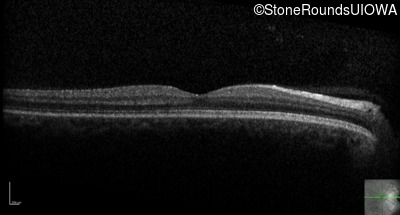

Optical Coherence Tomography - Left - 20/200

Exemplar / OCT Stack

OCT Stack